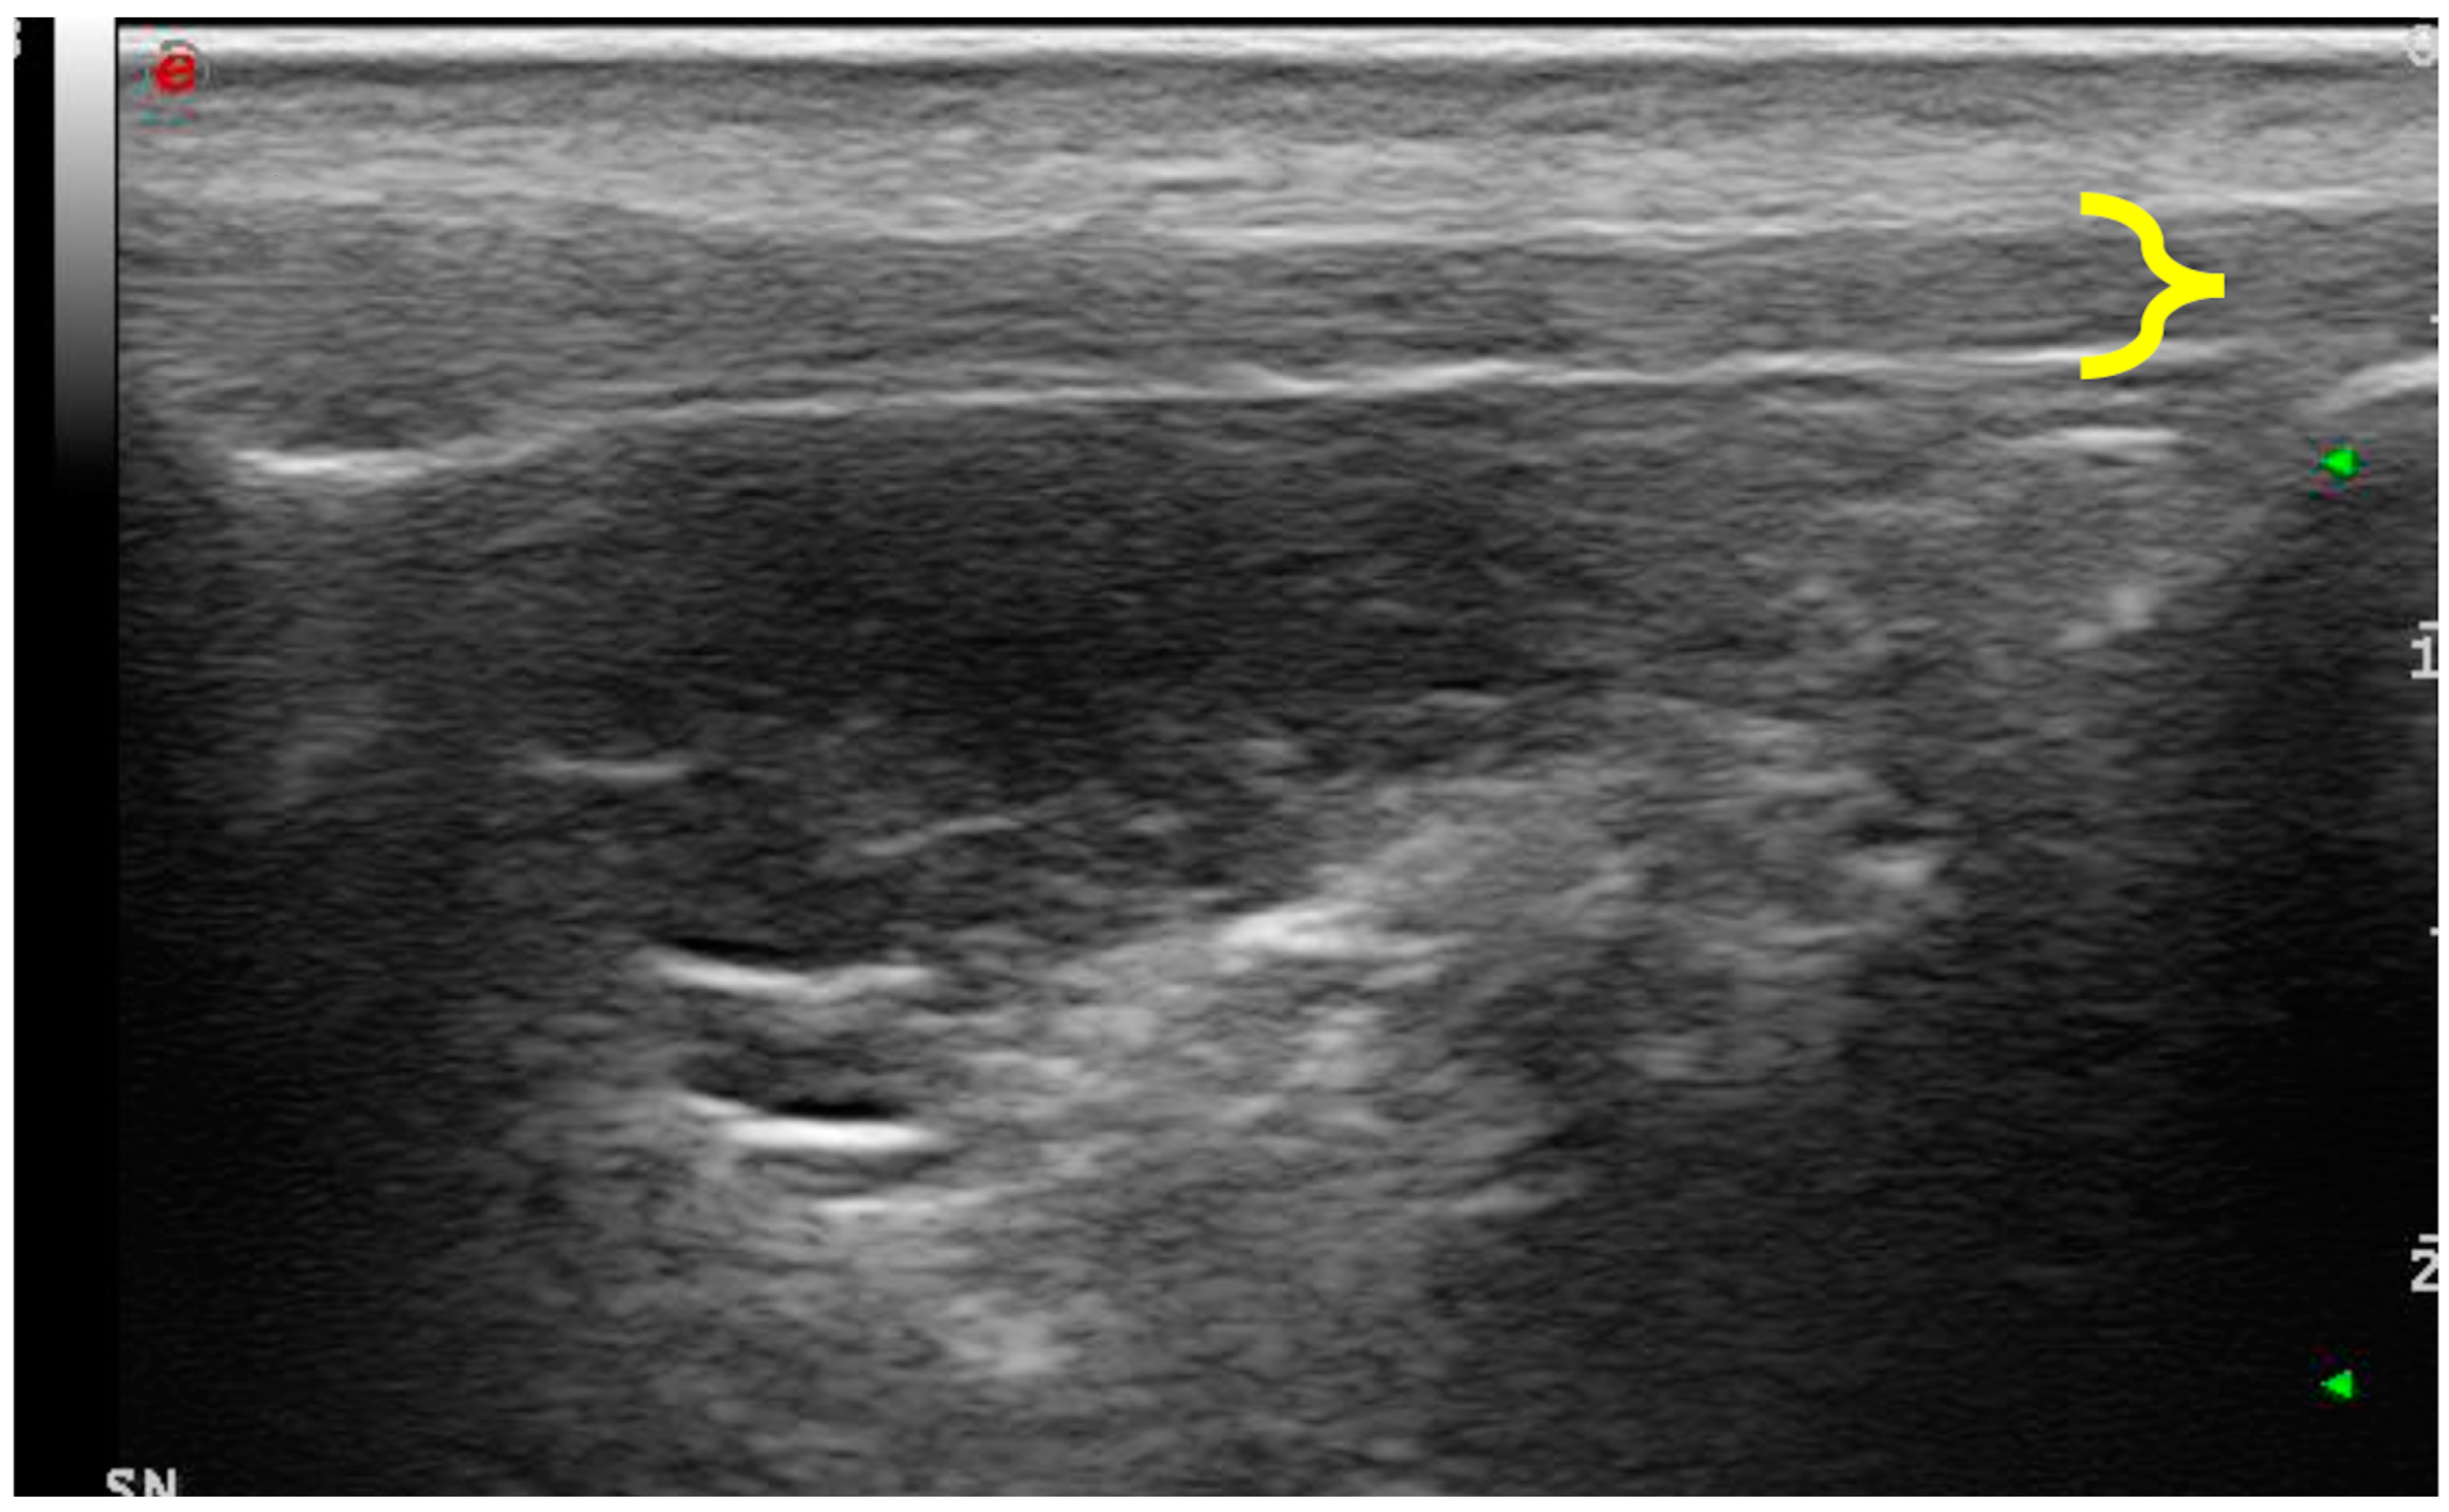

- Consistency between the elastogram and the underlying B-mode ultrasound image;

- Blue coloration of the skin and dermal tissue because they are harder than the patellar ligament;

- Green coloration of the marker (green coil). Thus represents real-time feedback on the quality of the strain image acquisition.